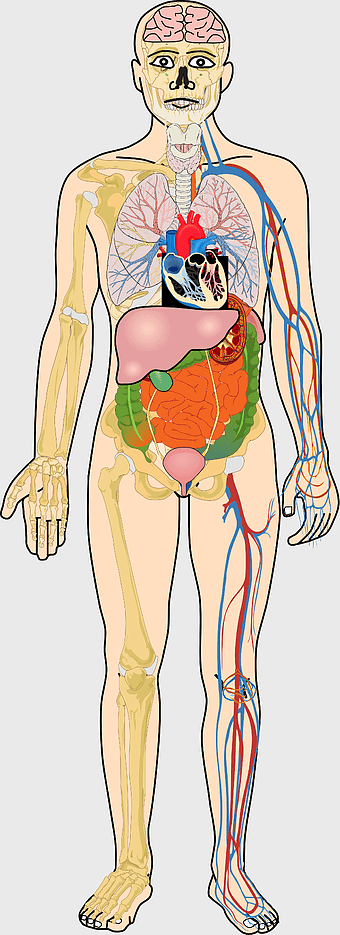

Human internal organs illustration, heart and lung anatomy, kidney and liver diagram, brain and stomach structure, medical organ chart, human body systems visual, educational anatomy graphics, PNG

- human internal organs illustration

- heart and lung anatomy

- kidney and liver diagram

- brain and stomach structure

- medical organ chart

- human body systems visual

- educational anatomy graphics